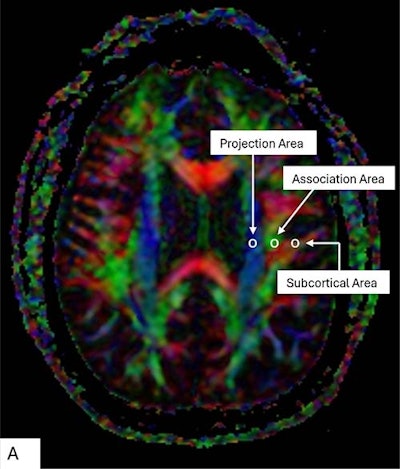

Color display of diffusion tensor imaging indicating the distribution of projection fibers (z-axis: blue), association fibers (y-axis: green), and the subcortical fibers (x-axis: red). Three regions of interest are placed in the area with projection fibers (projection area), association fibers (association area), and subcortical fibers (subcortical area) to measure diffusivities of the three directions (x, y, z).RSNA